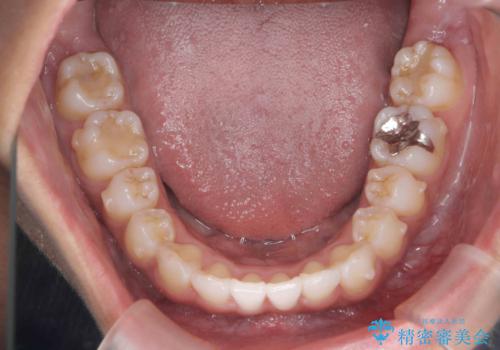

- 前歯のガタつき、突出感のある前歯の改善を求めて来院されました。

前歯の角度を改善し審美性を高めるとともに、奥歯のガタつきも並べ直すことで安定した咬合関係の確立を目指します。

歯列の側方拡大をしっかりと行ったことで歯を抜かずに前歯の角度をしっかりと改善することができました。